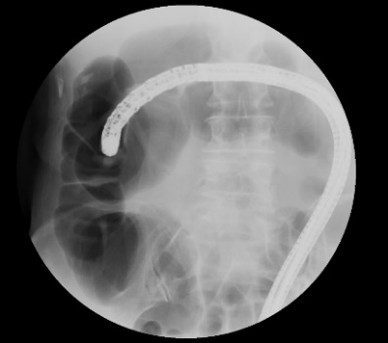

X線TV室

主に大腸内視鏡検査・消化器造影検査などを行っています。